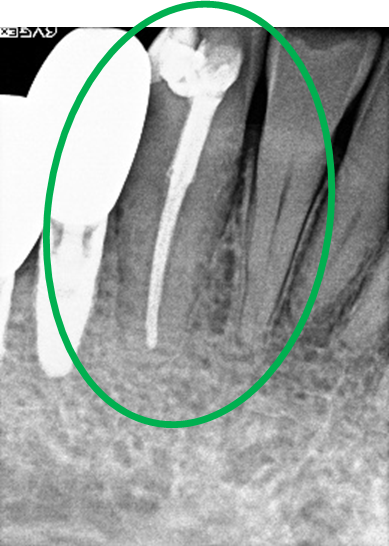

女性Hさん 60代(オールセラミック冠・インプラント)

主訴

右下のブリッジがゆらゆら動く。

治療内容

ブリッジの支台になっている奥の歯が、被せ物の中で虫歯になり、支台の役割を果たさず、前方の歯のみで支えられていました。前方の歯をそのままにして、後方の部分を切り離すと、そのまま取れてきました。中は、虫歯で歯根しか残っていない状況でした。この歯は、根管治療後、単独でオールセラミック冠を被せ、歯のないところにインプラントを埋入しました。

所感

今回の治療法には、次の3つの方法があります。

(1)虫歯になっていた歯の根管治療をし、土台を入れ、また再びブリッジにする。しかし、虫歯になっていたほうの歯は、ブリッジの支台として使うには、心もとなく長持ちしない可能性が高く、今度問題が生じたときには抜歯になる。

(2)虫歯になっていた歯に、単独で被せ物をし、歯のないところに1本だけの部分入れ歯を入れる。取り外しの入れ歯なので、自分の歯のような感覚で噛むことはできない。この方法も歯のない部分の負担を欠損の両側の歯に負担してもらうため、長持ちしない可能性が高い。

(3)虫歯になっていた歯に、単独で被せ物をし、歯のないところにインプラントを埋入する。欠損している部分の負担を前後の歯に負担させないので、歯を守ることができる。また、自分の歯と同じ感覚で食事をすることができる。

患者さんは、3つ目の方法を選択されました。一番長持ちし、これ以上歯を失わないためには、最良の方法だと考えます。

オールセラミック冠(失活歯):¥104,500(税込)

インプラント:¥363,000(税込)

合計:¥467,500(税込)

Before

冠の中で大きな虫歯になり支台の役割を果たしていませんでした。

【インプラント埋入前】

冠はブリッジを切断しただけで取れてきました。軟化象牙質を取り除いたところ、歯根しか残っていない状況で保存できるかどうかのぎりぎりのところでした。

After